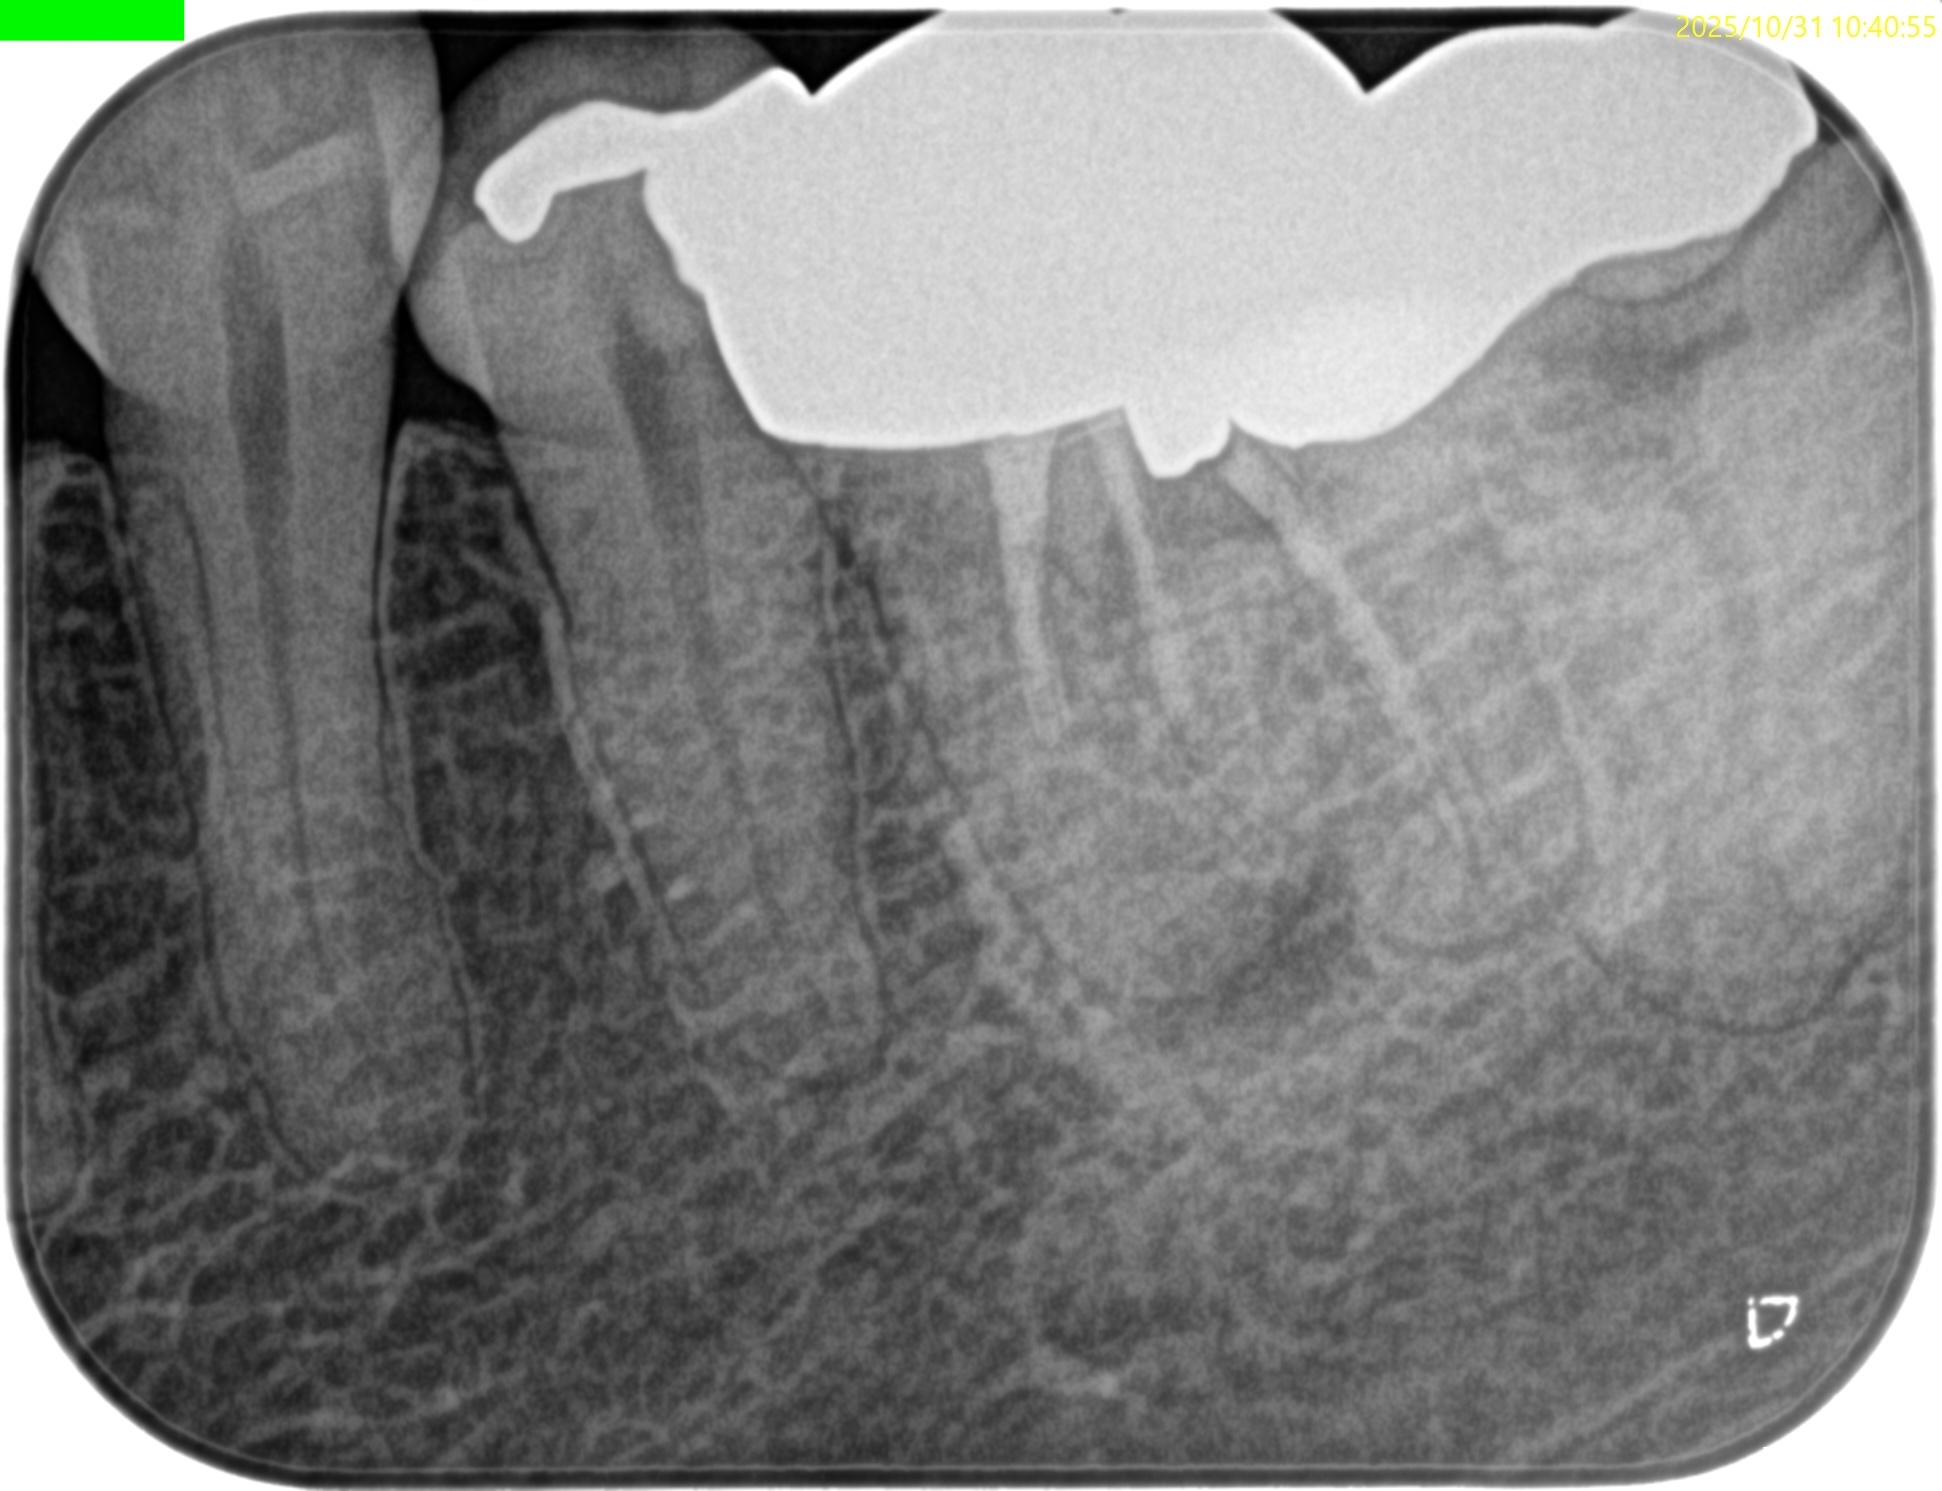

PA(2025.10.31)

PAでは上記の私の謎は解明できない。

#19の近心根には根尖病変は見えるが…

圧痛が強いのは#18近心だ。

意味がわからない。

ということで臨在歯の#18もCBCTを精査した。

#18

M

D

#18 Mのこの絵は縁下カリエスの可能性を示唆している。